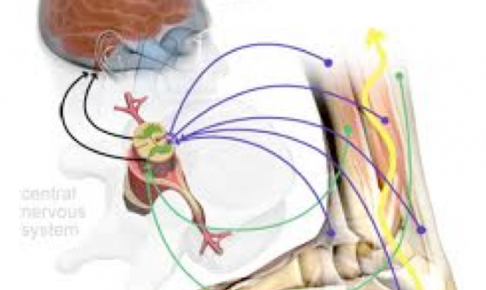

こんにちは!横浜本牧パーソナルトレーナー宮原崇です。 今日から8月ということで、個人的に1年のうちで一番好きな月なので、朝からワクワクしております。 さて、昨日の続きです。 ひざ痛の多くの方が足裏の感覚情報が低下して、そ…

こんにちは!横浜本牧パーソナルトレーナー宮原崇です。 今日は夏晴れでセミの鳴き声も心地よいです。 さて、午前のトレーニングセッションを終えてこれから午後の部となりますが、ひざ痛の方の多くが持っている身体の特徴をお伝えいた…